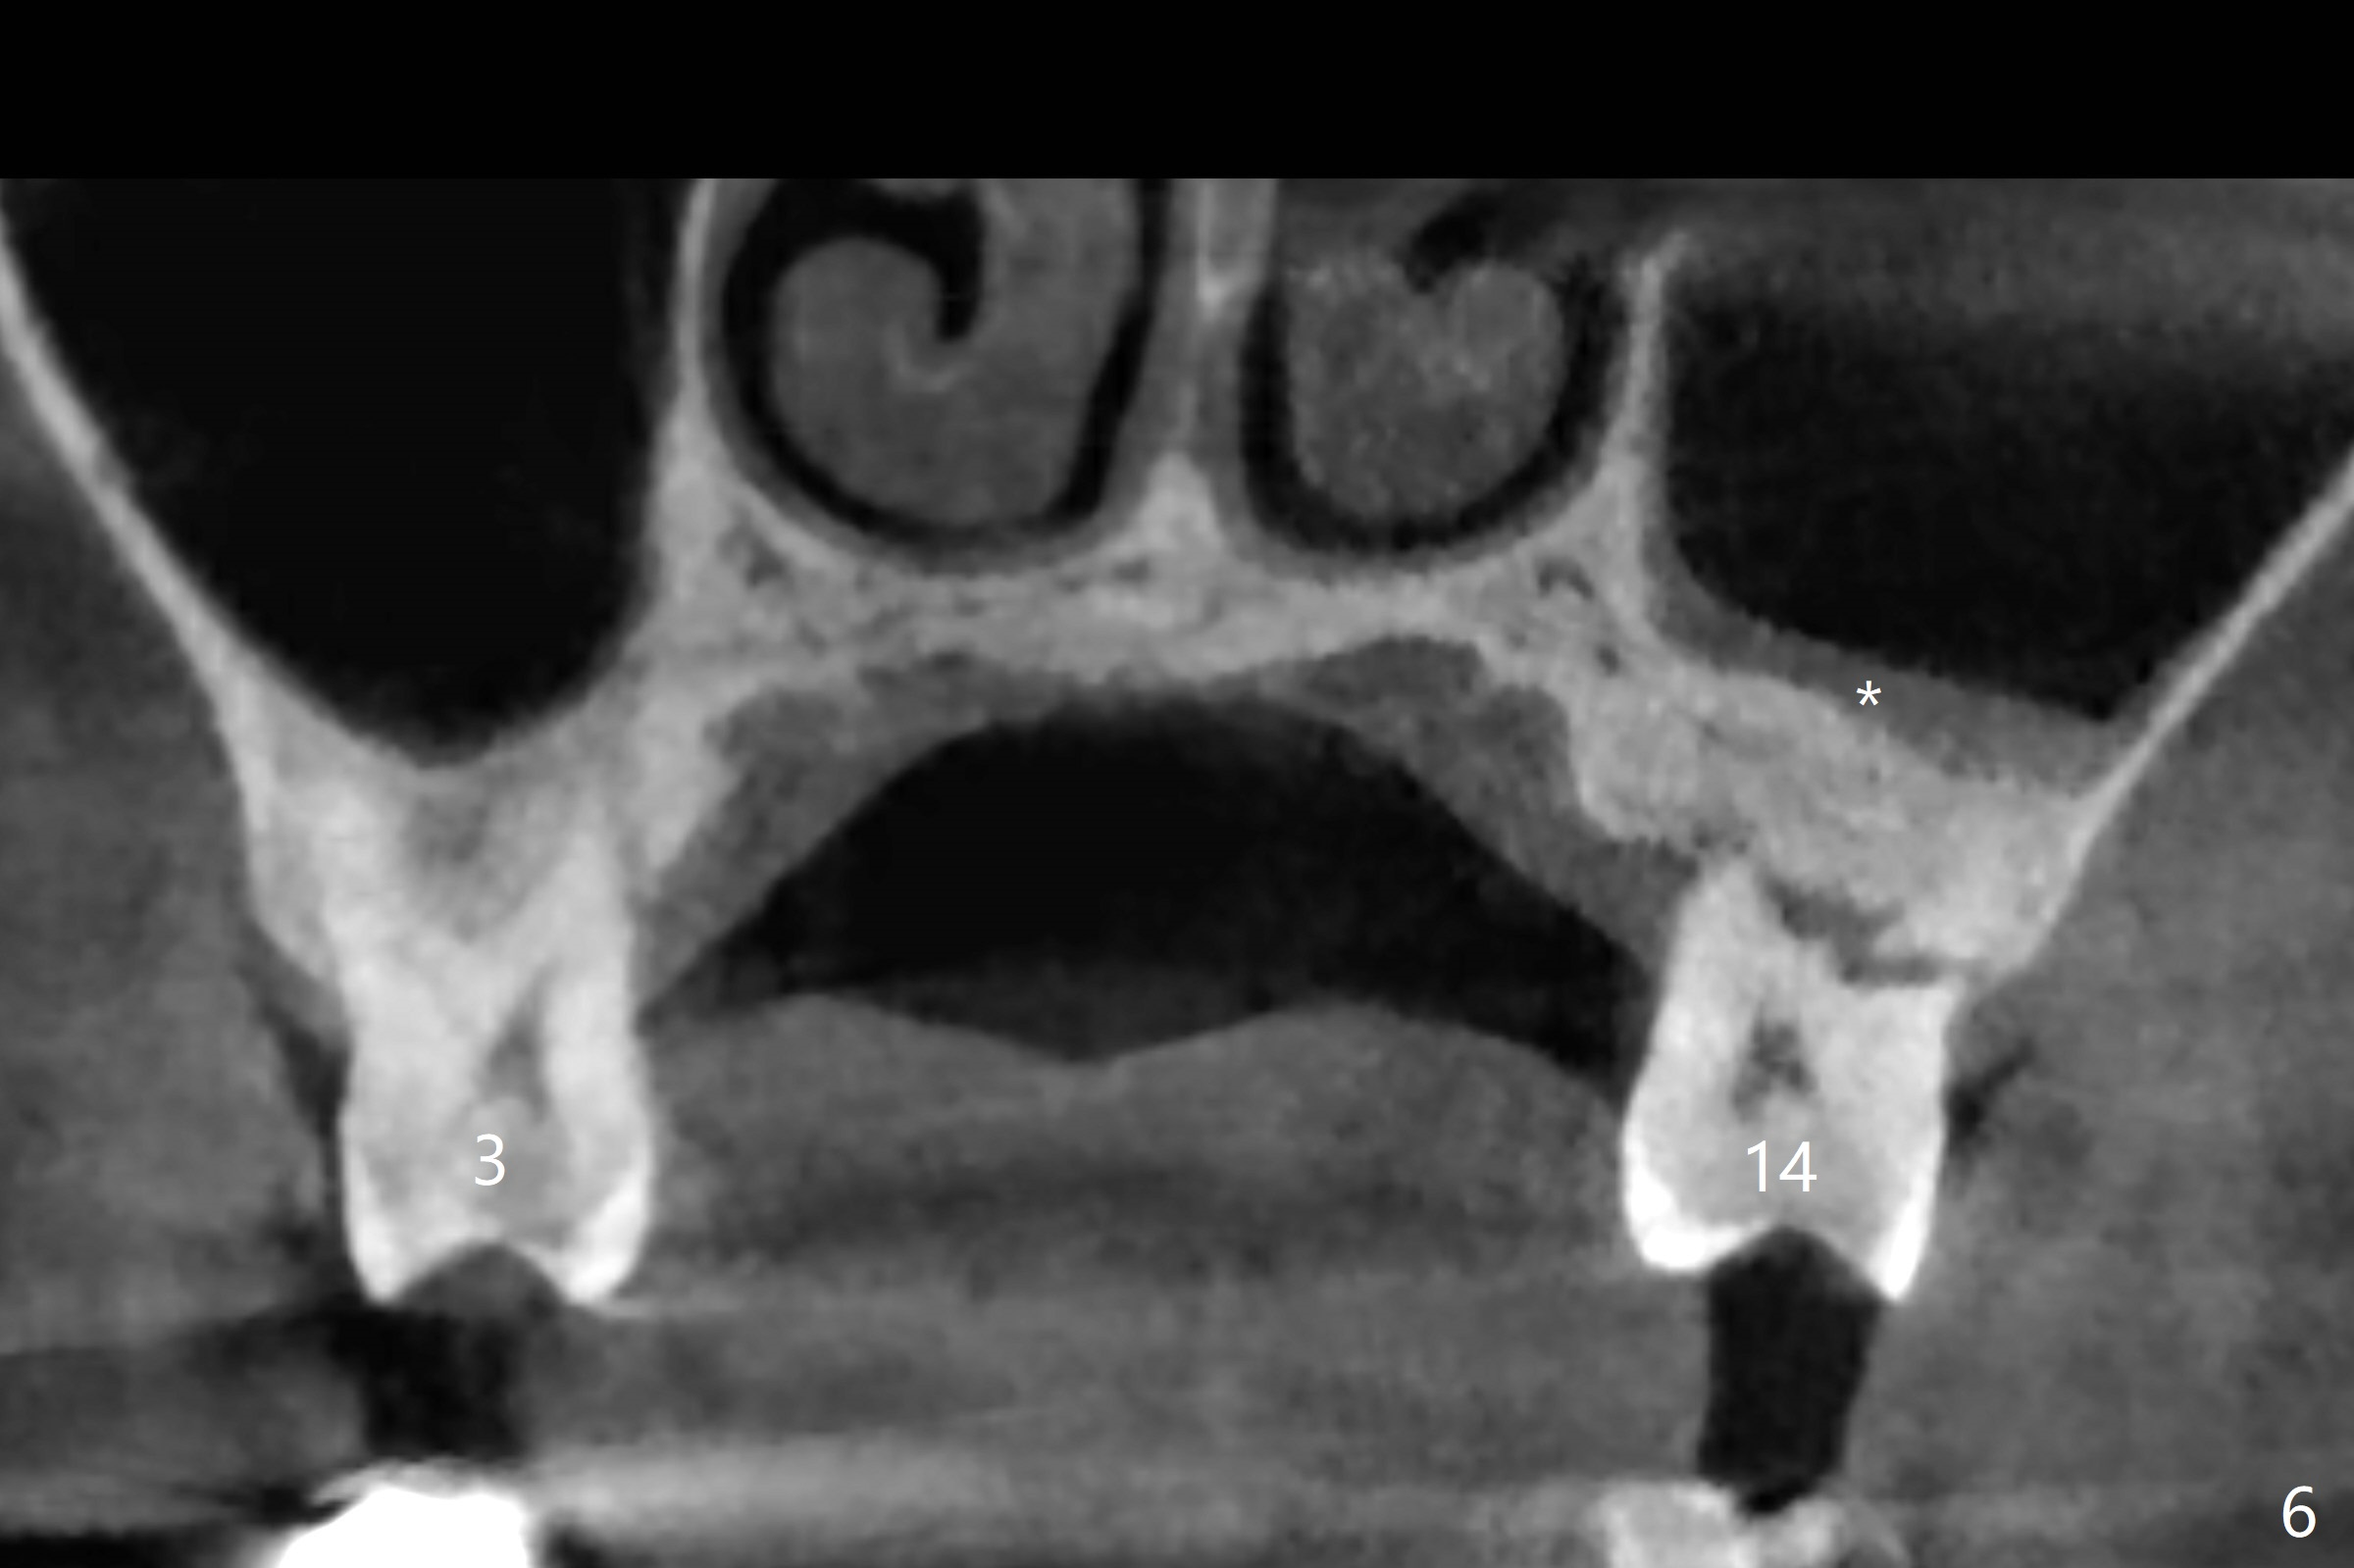

A 60-year-old man had buccal furca abscess at #14 with an unknown radiolucent lesion within the tooth five months earlier (Fig.1 *). Now the tooth is sensitive to cold. CBCT shows internal resorption involving the mesiobuccal and distobuccal roots (Fig.3,4 (axial section) *) with exits mesially (Fig.3 >) and buccally (Fig.2 ^). There is periapical radiolucency of MB (Fig.3,7) with the thickened overlying sinus membrane (Fig.3,5,6 (*), as compared to that over the tooth #3 (Fig.6)). Osteotomy will be established in the septum away from the lesion (Fig.8 red circle) and for 5 mm (Fig.5 (coronal section)). He is a heavy bruxer, loosening Ketac-cemented unipost. Use PRF to repair the defect associated with the MB lesion and sinus lift.